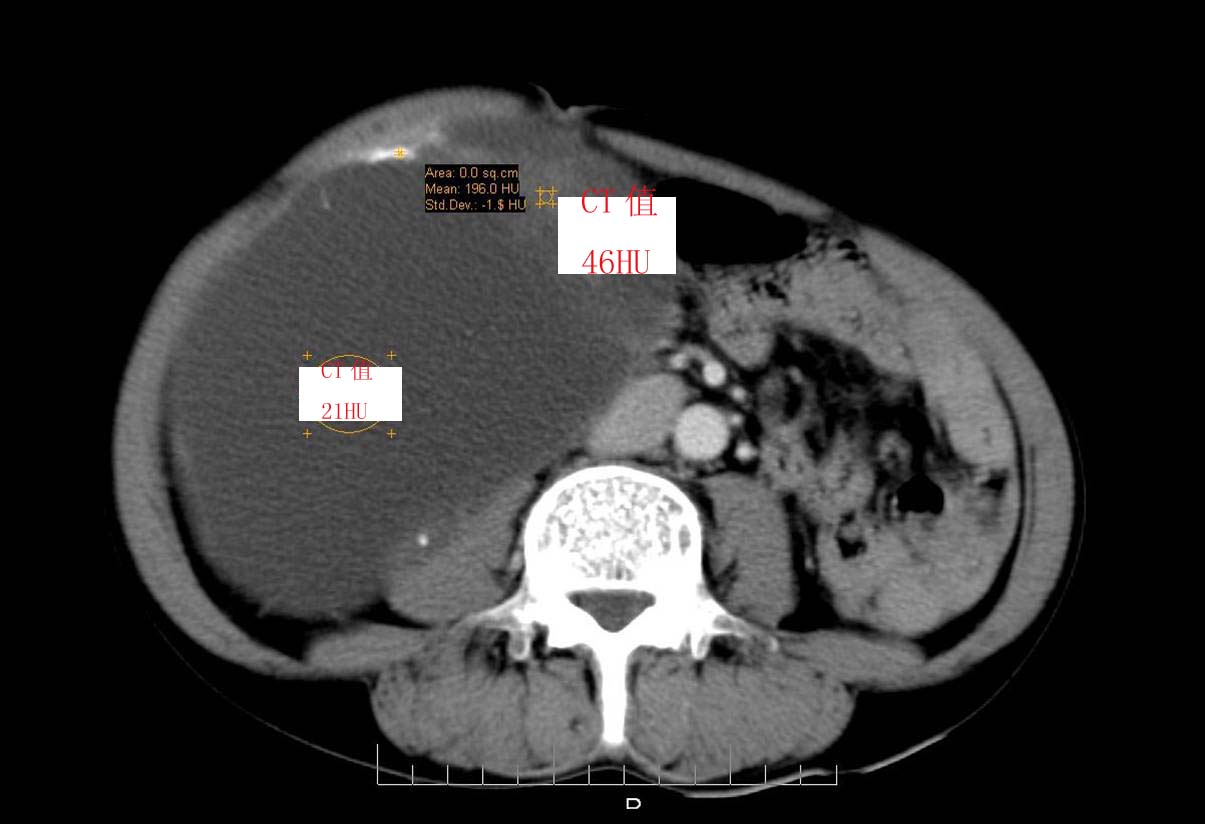

男性 60岁,腹部肿块4年余,肿块逐渐增大,活动性差,无血尿。

动脉期

ct值测量

考虑肾囊肿并囊内出血。

囊性肾癌可能性大

右侧多发性肾囊肿,其中之一巨大(不排除其为重复肾积水可能);右肾积水。

考虑右肾多发囊肿并出血

右肾脏巨大囊样影、囊壁有钙化,囊样影轻度强化有软组织成份。不除外畸胎瘤可能。

囊性肾癌可能性大,右肾多发囊肿。

巨大囊性肿块,囊壁较厚有强化,有团片状钙化,病灶内下方灶内见片絮状高密度影,增强有轻中度强化,考虑囊性肾癌可能性大

右肾上部巨大的囊实性影,实性部分轻度强化。壁有钙化。考虑右肾囊腺癌。右肾盂积水。

定位;肾明显与病灶杯口相交,可以肯定病变来自右肾。

定性;病灶囊性为主,前下部含实性成分,及钙化,部分壁厚薄不均。

肾囊实性病变有;1,囊性肾癌2,囊性肾瘤。3,复杂囊肿。4,重复肾伴积水。然2、3壁相对规则。

综上考虑;囊性肾癌》重复肾伴积水。